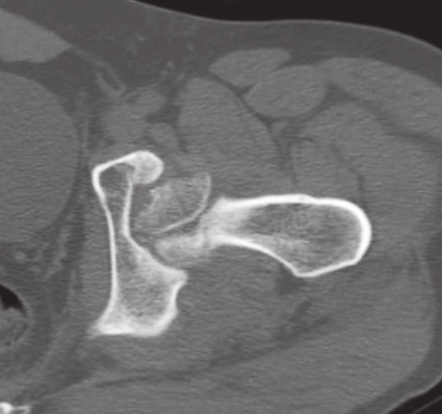

患者1周前于车祸中受伤,受伤时患者位于副驾驶座位,所坐车辆与前车追尾。车辆发生撞击后,患者出现左髋部畸形、剧烈疼痛及活动障碍。外院影像学检查诊断为左髋关节脱位、左髋臼骨折、左股骨头骨折(图4~图6)。

图5 闭合复位左髋关节后,CT三维重建示左髋臼后壁骨折

图6 CT断层示股骨头前内部分粉碎性骨折,并翻转移位